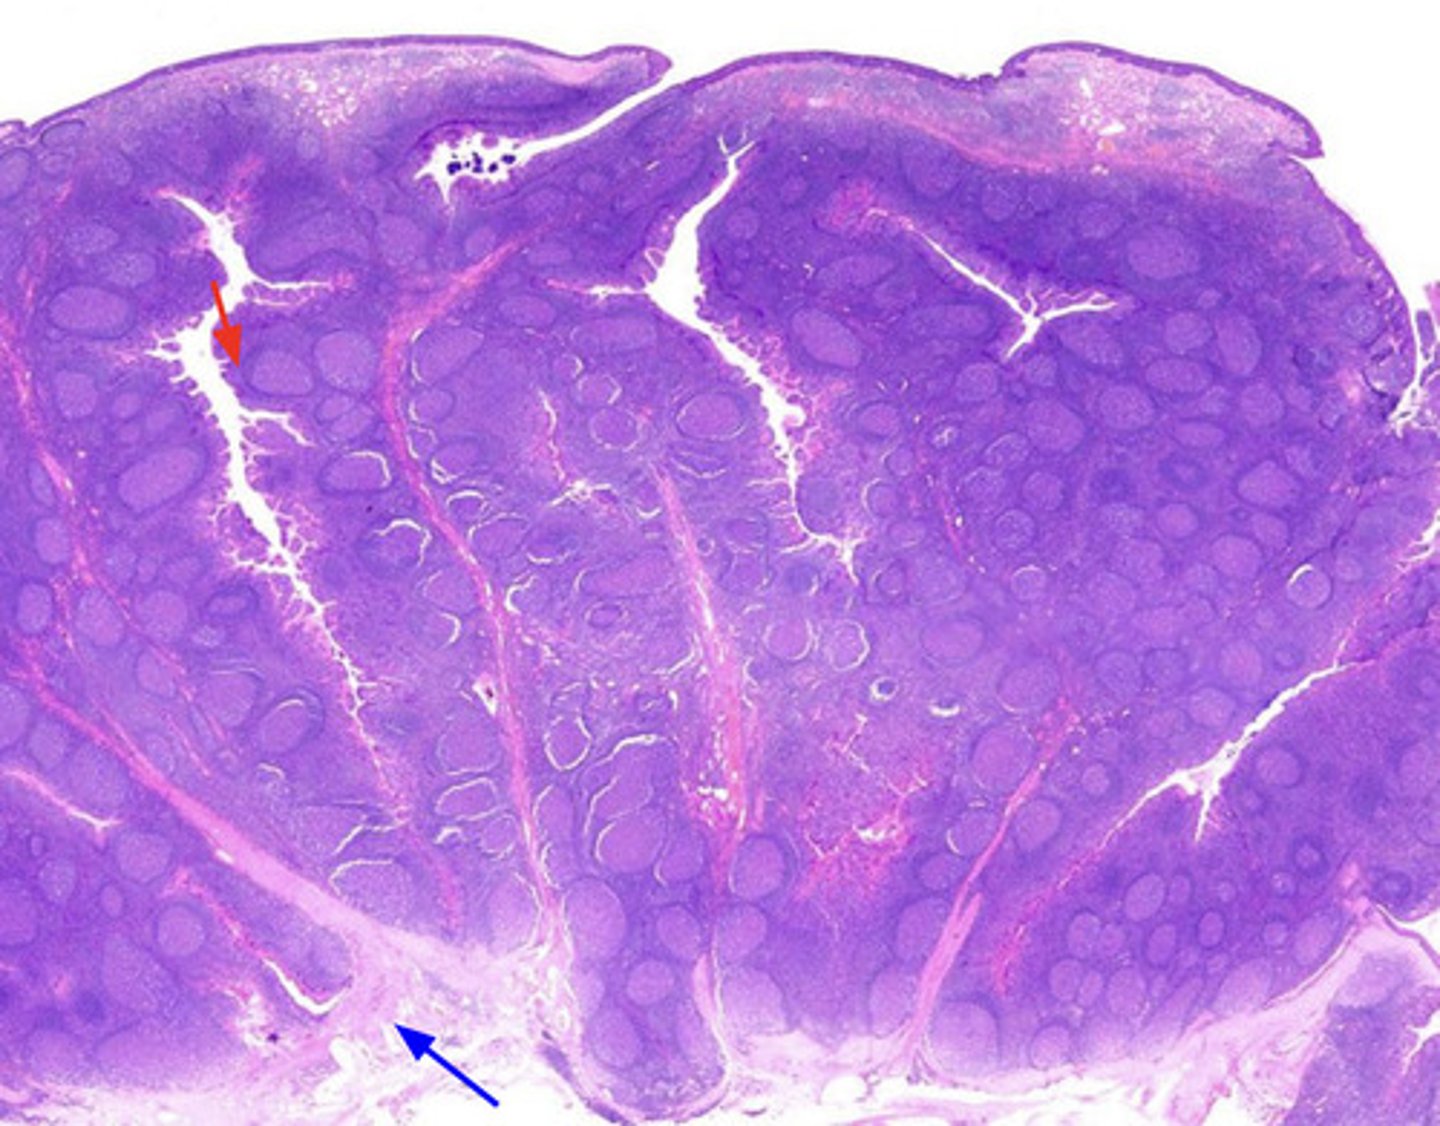

red pulp (spleen)

-is the dark red tissue in the spleen containing sinusoidal capillaries, connective tissue fibers, and immune cells like macrophages, plasma cells, and lymphocytes.

-It destroys old red blood cells, removes pathogens and toxins

-facilitates lymphocyte movement between splenic tissue and blood.

white pulp (spleen)

has whitish appearance in a fresh spleen. Lymphocytes, macrophages surrounding small branches of splenic artery